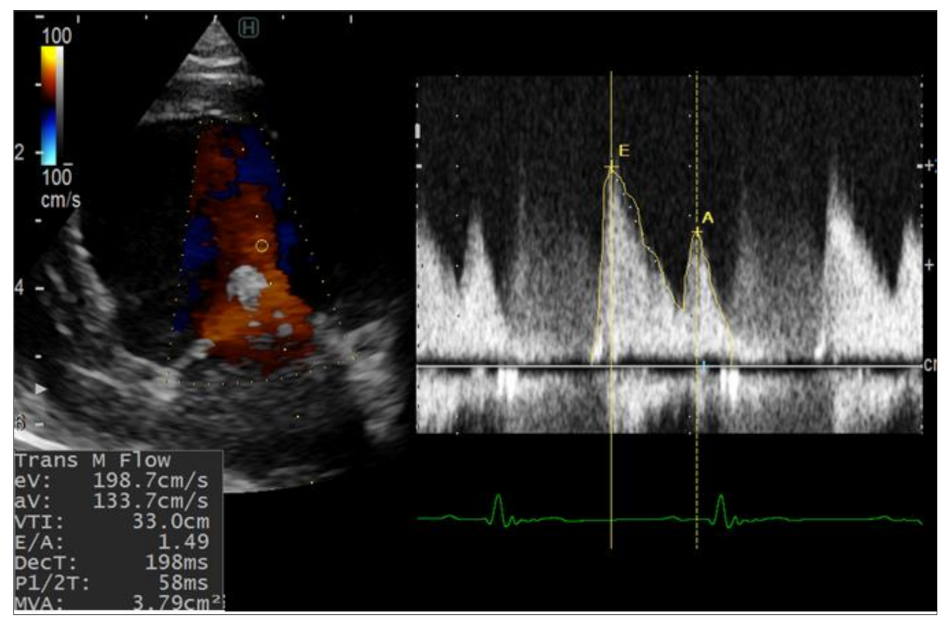

The detailed echocardiographic parameters are listed in Table 1. The left ventricular dimensions showed no dramatic changes after the surgeries. The fractional shortening was increased postoperatively in both dogs compared with the baseline, but this increase was much higher in dog 2. The mitral inflow velocity waves (E and A) were significantly increased after the operation and throughout the investigation period (Figure 2). The mitral valve orifice in both dogs was slightly narrowed after the operations (2–3 mm difference) at the second and third weeks. In addition, the stenosis was not progressive and both dogs showed slight enhancement of the mitral orifice at the fourth week. Concomitantly, the LA/Ao, early diastolic inflow to myocardial velocity (E/e’), and mitral valve regurgitation velocity (MR) were increased in both dogs after surgery.

Figure 2. Pulsed-wave Doppler echocardiography for evaluation of the mitral inflow from left apical four-chamber view after TEER implantation. Increase in E wave values was observed after TEER implantation. eV, early diastolic filling velocity; aV, atrial filling velocity.